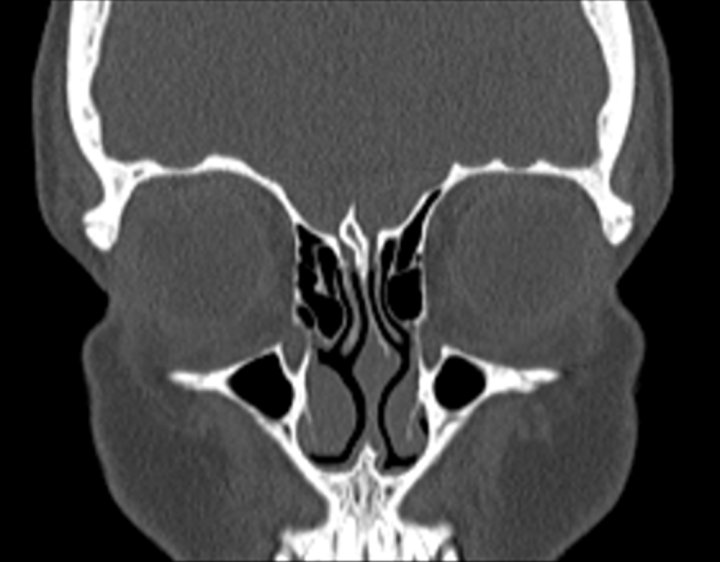

Click any image for labels.